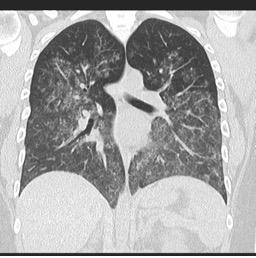

o HRCT: difúzne sklené opacity a alveolárna konsolidácia.

Difúzna alveolárna hemorágia spôsobená vaskulitídou

Zdroj: radiopaedia.org